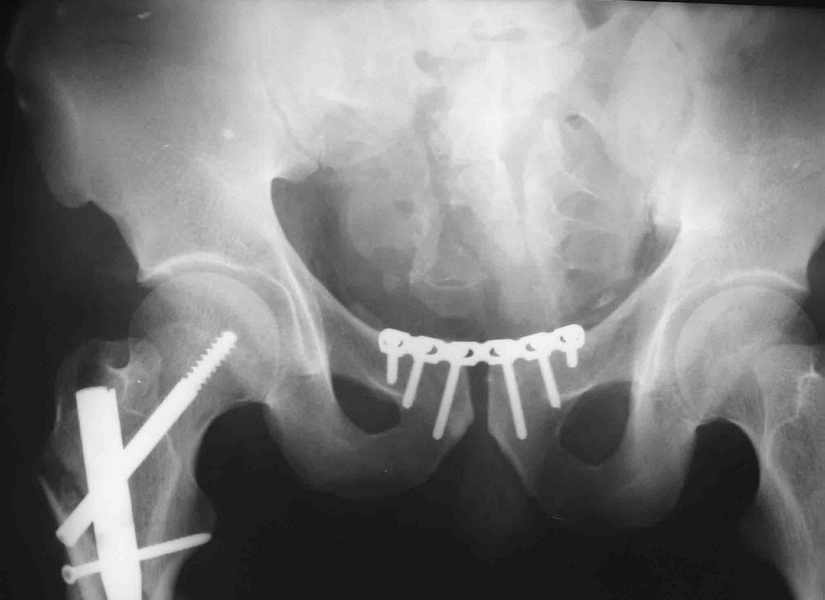

извините за опоздание , вот фотографии

Репозиция действительно очень неплохая, но чтобы уменьшить риск развития поздней нестабильности, в такой ситуации лучше выполнить синтез лонного сочленения пластиной и оставить аппарат месяца на 2.

В вашем случае при таком диастазе надежнее будет зафиксировать задние и передние отделы(сзади -винты, спереди -пластина).